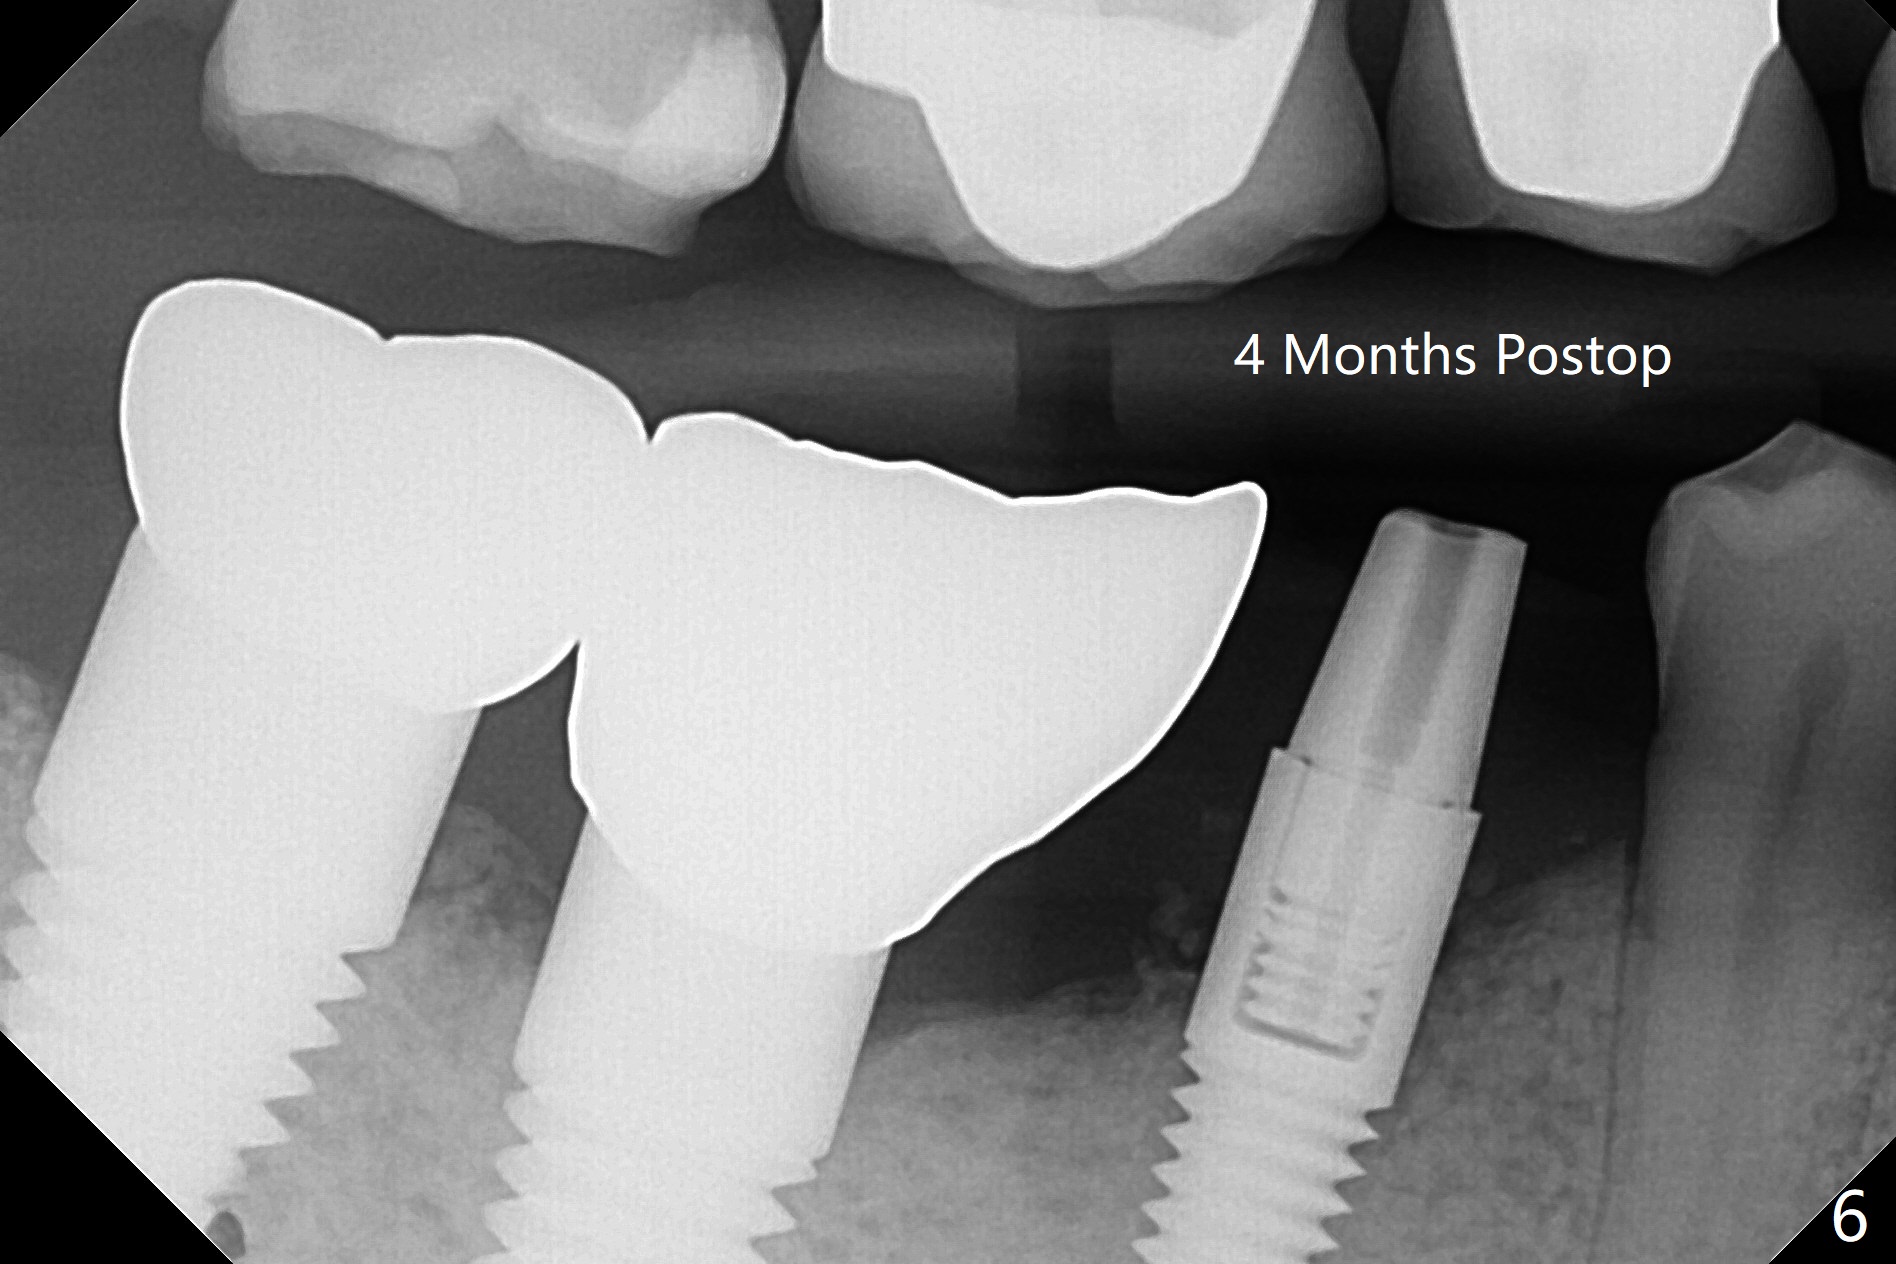

徒手即刻种植缺点是钻洞深度控制不易,尤其是术前设计是骨水平植体,而术中决定使用软组织水平植体。当3毫米reamer达到14毫米深度(骨水平)时,略感到根尖骨质长度。可欣的是4乘17毫米软组织水平植体取得初步稳定性(图二),即刻放置基台(3.5乘5毫米)后,骨粉放入颊侧间隙,有意地把骨粉推向远中(图二:*),好像植体接近颏神经(图二:红色),不过术后没有神经麻木现象,术后分析术前CT表明植体离神经相当远(图三)。术后四个月病人回来做修复,这时我们不关心深部神经了,重点是牙槽嵴周围骨质与植体愈合如何。可以使用sensor 1 (一号传感器,图四:1)和根尖片固定器(黄色,这样减少病人疼痛,恶心,容易放置,拍摄影像好,平行)或者sensor 2(图四:2)加咬翼片固定器(红色,同样容易放置,拍摄影像好,平行,植体螺纹清晰);为了拍摄下颌牙齿多些,传感器放低些(相对于固定器,图四,五),结果得到的信息足够(图六),好像植体已经整合,接着取模。There is no residual cement immediately post cementation with a small escape hole occlusally (Fig.7).